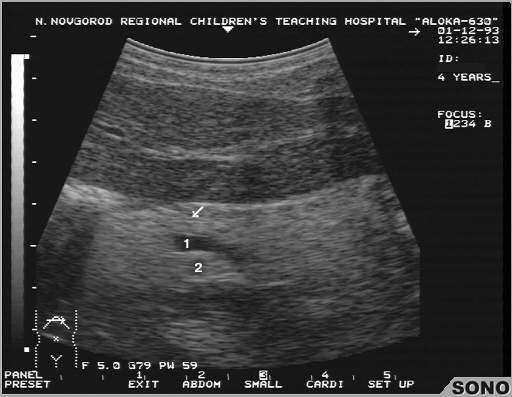

Показатель в норме должен быть немного ниже среднего. На экране монитора выдается он  следующим образом – проходимость средняя, структура однородная. Клетки паренхимы расположены так, что ткань является довольно плотной и пройти ультразвуковым волнам сквозь них не так уже и просто. Однако, средняя проходимость является вполне нормальным показателем, в то время как пониженная – это проявление гепатита в острой форме или наличие других заболеваний. Это значит, необходимо дообследование (биопсия, анализ крови, рентгенологическое исследование, холангиография и т.д.) с целью уточнения диагноза.

Большинство поражений органа при повышенной эхогенности имеют диффузный характер, что значит поражение паренхимы не полностью, а местами. Ультразвук в таком случае обнаруживает неоднородные участки в диаметре до двух сантиметров, которые могут быть проявлением одного из перечисленных выше заболеваний.